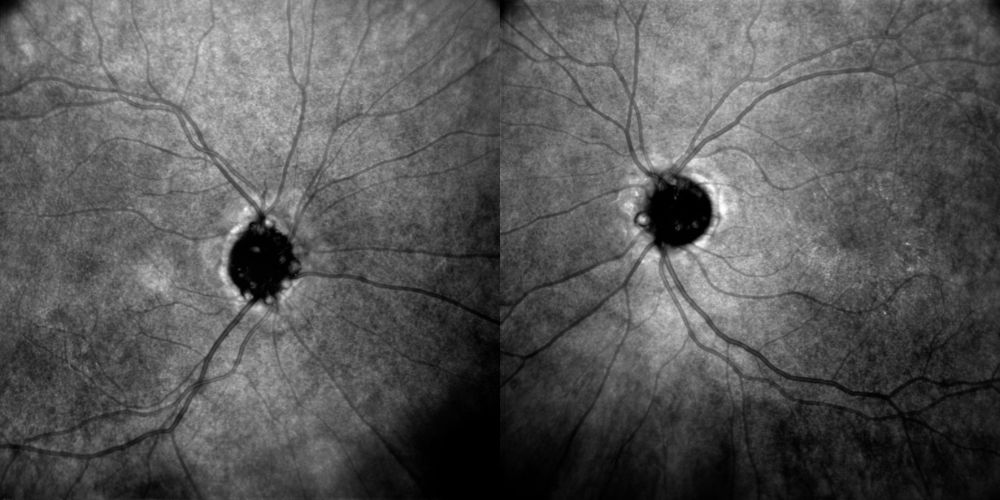

Autofluorescenza del fundus

La FAF evidenzia in entrambi gli occhi molteplici foci iperautofluorescenti, intensi, nodulari, in parte confluenti e multilobulati, localizzati centralmente e al margine della papilla. Il segnale è particolarmente brillante e grossolano, compatibile con drusen superficiali visibili; tale aspetto contrasta con il pattern atteso nel papilledema, dove non si osservano tipicamente noduli iperautofluorescenti così ben definiti. Nell’occhio sinistro il carico lesionale appare leggermente più esteso e confluente.

Figura 2. Autofluorescenza del fundus. A sinistra, OD con multipli foci iperautofluorescenti intensi, nodulari e confluenti a carico della testa del nervo ottico, con interessamento del margine papillare. A destra, OS con foci iperautofluorescenti più numerosi e confluenti rispetto all’occhio controlaterale, a morfologia multilobulata e distribuzione centrale e marginale, compatibili con drusen papillari superficiali.